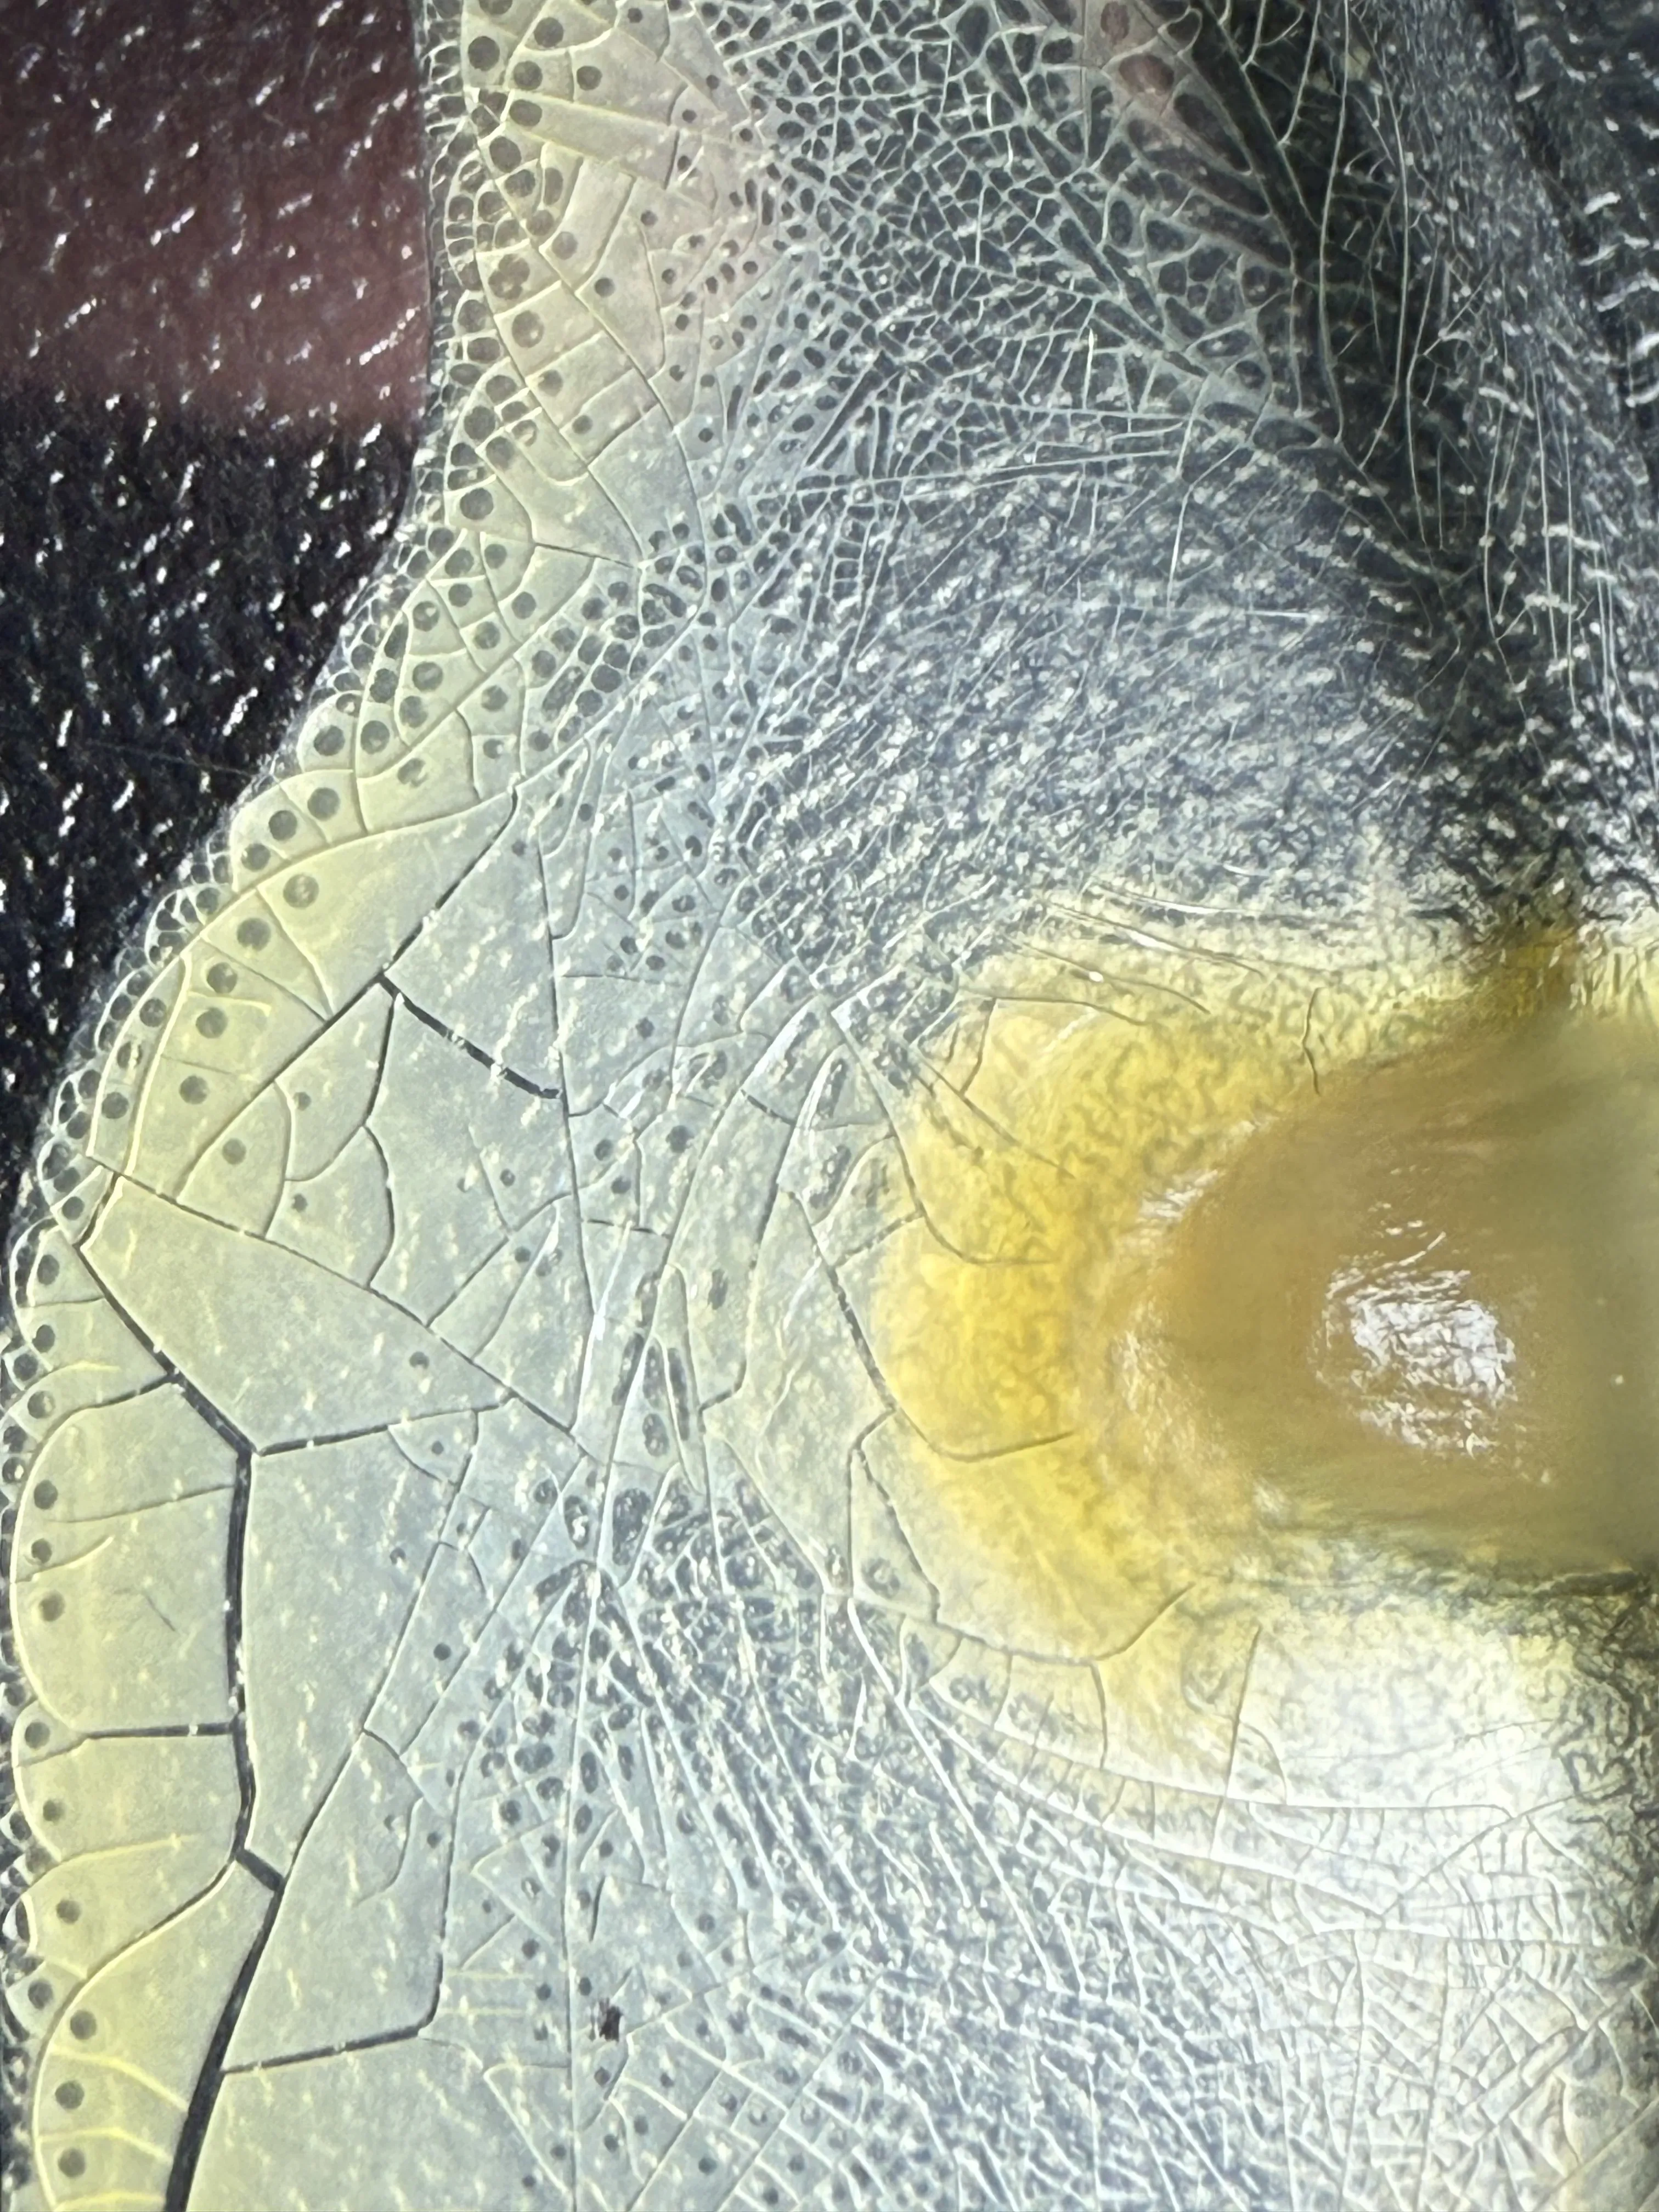

Галерея исследования

Результаты покадровой 4K съёмки образцов плазмы крови: пробирки, колбы и микроскопические снимки процесса коагуляции.